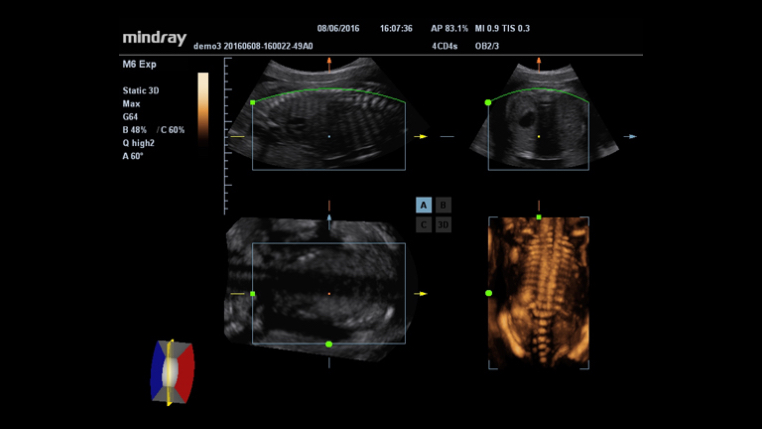

3D/4D imaging technology delivers a range of tools that help take advantage of the full value of volume data. With rich rendering modes, more information on fetus structure is made available to make a more confident diagnosis.